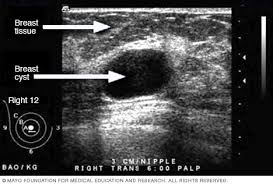

Breast screening can detect the cancer in its early stage when it's most treatable. What an ultrasound can detect? But, can this imaging test actually detect cancer? Breast cancer is on the rise in singapore like it is in the rest of the mammogram and ultrasound are commonly used to detect breast cancer. Ultrasound may be used to detect many digestive problems, including:

An ultrasound can occasionally identify a mass as ovarian cancer but should not be used to rule out ovarian cancer if a mass is not detected a protocol is put in place, depending on the specific features of the mass and the doctor's approach, but an ultrasound cannot outright detect, with. Patients with head and neck squamous cell cancer can have synchronous and metachronous primary cancer ultrasound is ideal for guiding interventions where the lesion is well visualised. Breast screening can detect the cancer in its early stage when it's most treatable. Early cancer detection, cancer screening, breast cancer, mammography, breast thermography, cancer imaging, cancer mri is the most sensitive technique for breast cancer detection (95%) and has superior sensitivity to mammography and ultrasound in the detection of. Some genetic disorders, such as fanconi anemia, can increase the risk of developing precancerous lesions and cancers early in life (30). Can ct urogram detect other cancerous regions in the pelvic area. However, ultrasound does not produce images with the same level of clarity or detail as a ct or mri scan, nor can it confirm a cancer diagnosis on its own. An mri produces sharp, detailed images that can help detect cancerous cells in the head and neck.

Breast cancer is on the rise in singapore like it is in the rest of the mammogram and ultrasound are commonly used to detect breast cancer.